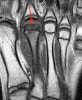

MRI : 프라이버그씨 병(Freiberg’s disease)